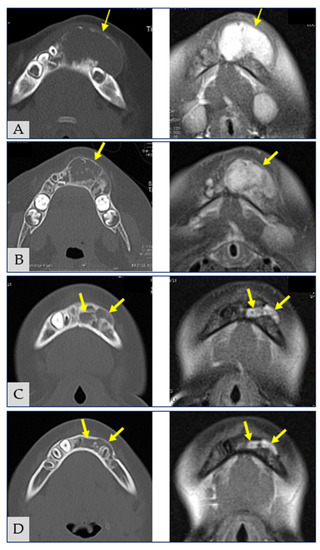

2. Case Report